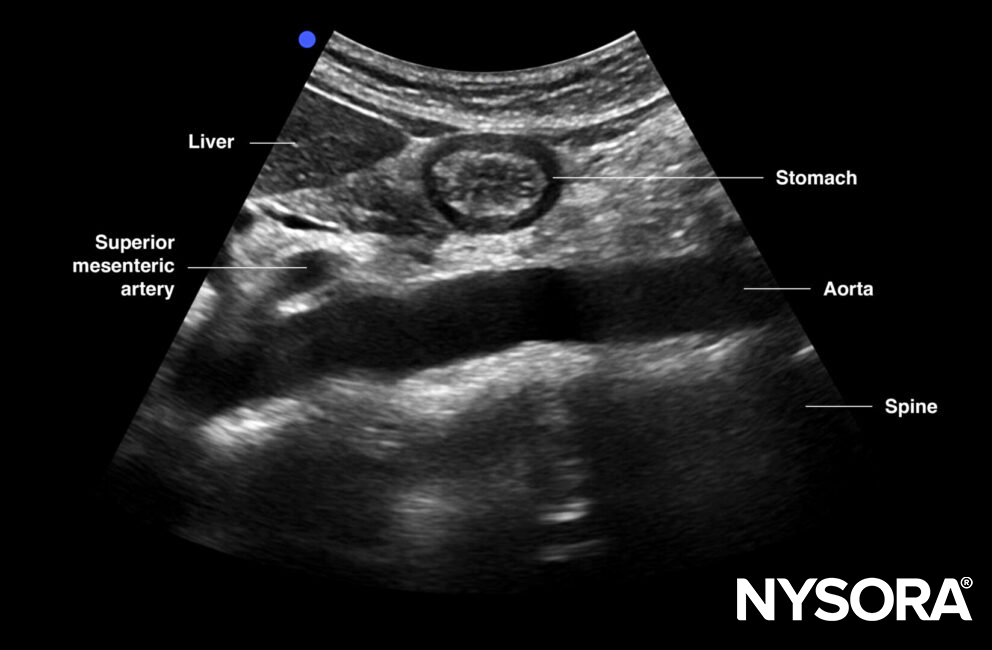

Mid aorta

Transverse view of mid aorta: superior mesenteric artery, aorta, renal vein, splenic vein (anterior to SMA), and left renal vein (between SMA and AA), spine, transverse colon, pancreas, liver

Transverse view of the mid abdominal aorta.